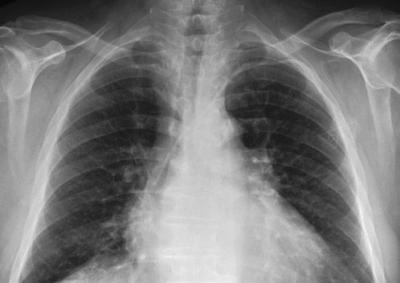

यानंतर डॉक्टरांनी महिलेच्या छातीचा एक्स-रे काढला. त्यात तिच्या फुफ्फुसाच्या उजव्या बाजूला प्लास्टिकसारखी वस्तू आढळून आली. ही वस्तू गोल आकाराची होती.